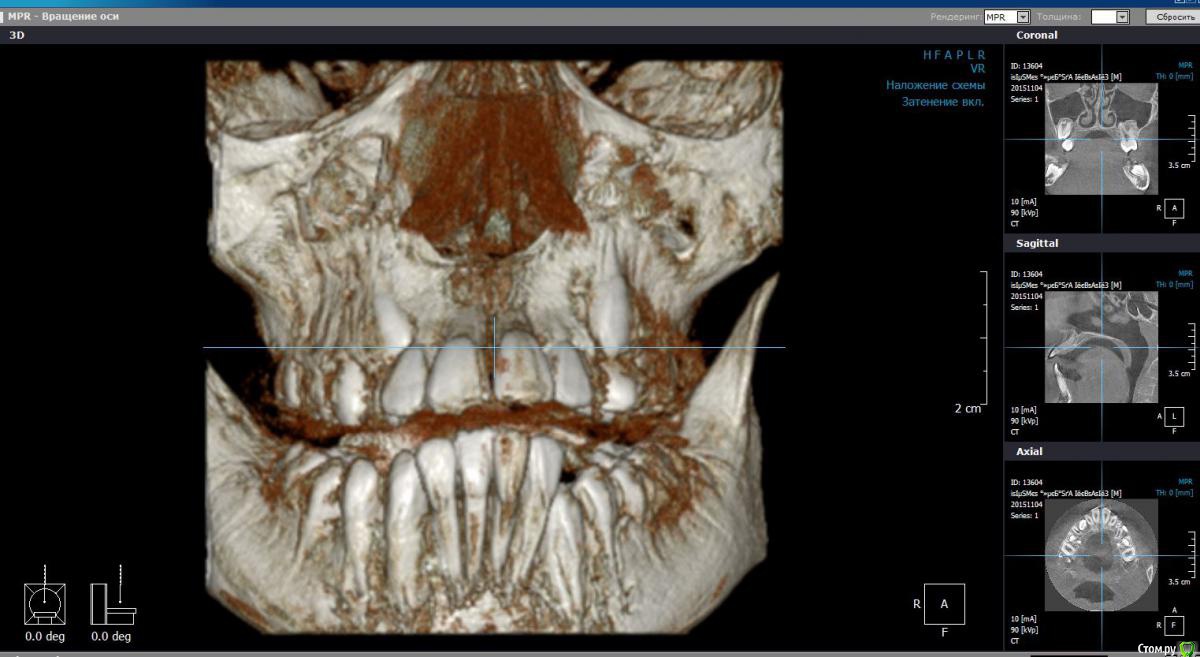

Monkey Опубликовано 27 апреля, 2016 Поделиться Опубликовано 27 апреля, 2016 (изменено) Коллеги! Прощу совета и помощи. Кто как справляется с выраженным 2-1. Парнишке 12 лет. Со слов мамы ни вредных привычек, ни родовой травмы не было. Опять же со слов мамы, есть серьезное искривление перегородки носа ( ЛОР сказал можно править только после 17 лет).Сейчас удалили зачатки 38,48. Ждем когда созреют 18,28.Как вести таких пациентов? и реально ли обойтись без хирургии? Когда начинать лечение и на каком аппарате?P.s. если у кого-то были похожие вылеченные случаи, буду благодарна за демонстрацию. Изменено 27 апреля, 2016 пользователем Monkey Ссылка на комментарий

Yana guapa Опубликовано 27 апреля, 2016 Поделиться Опубликовано 27 апреля, 2016 почему клкт делали с открытым ртом? в итоге проекции , которые вы выложили - не информативны. лучше "классика" - снимки (трг) , фото (причем полноценный набор:фас, профиль, профиль с улыбкой, обнажение резцов в покое...) это все имеет значение при составлении плана лечения и выбора методики. Ссылка на комментарий

Monkey Опубликовано 28 апреля, 2016 Автор Поделиться Опубликовано 28 апреля, 2016 почему клкт делали с открытым ртом? в итоге проекции , которые вы выложили - не информативны. лучше "классика" - снимки (трг) , фото (причем полноценный набор:фас, профиль, профиль с улыбкой, обнажение резцов в покое...) это все имеет значение при составлении плана лечения и выбора методики. Проблема в том, что ничего и нет. На консультации сказала маме, что надо ждать созревания и прорезывания зубов. но потом еще раз КТ посмотрела и решила, что надо действовать сейчас! Буду вызывать на модели и снимки. Ссылка на комментарий